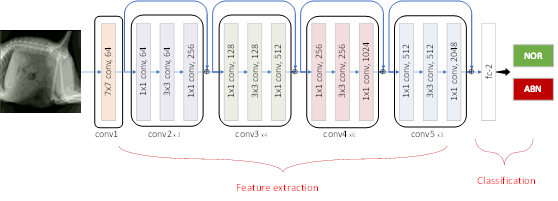

AI 모델 상세 설명서 다운로드 AI 모델 다운로드ResNet 50 기반 구현

주요 분류 모델은 (He et. al., Deep Residual Learning for Image Recognition, CVPR 2016) 결과에 기반하여 적용

학습을 위하여 모든데이터는 수평으로 된 이미지로 전처리 과정을 거침

주요 학습을 위한 구현 상세는 다음과 같음